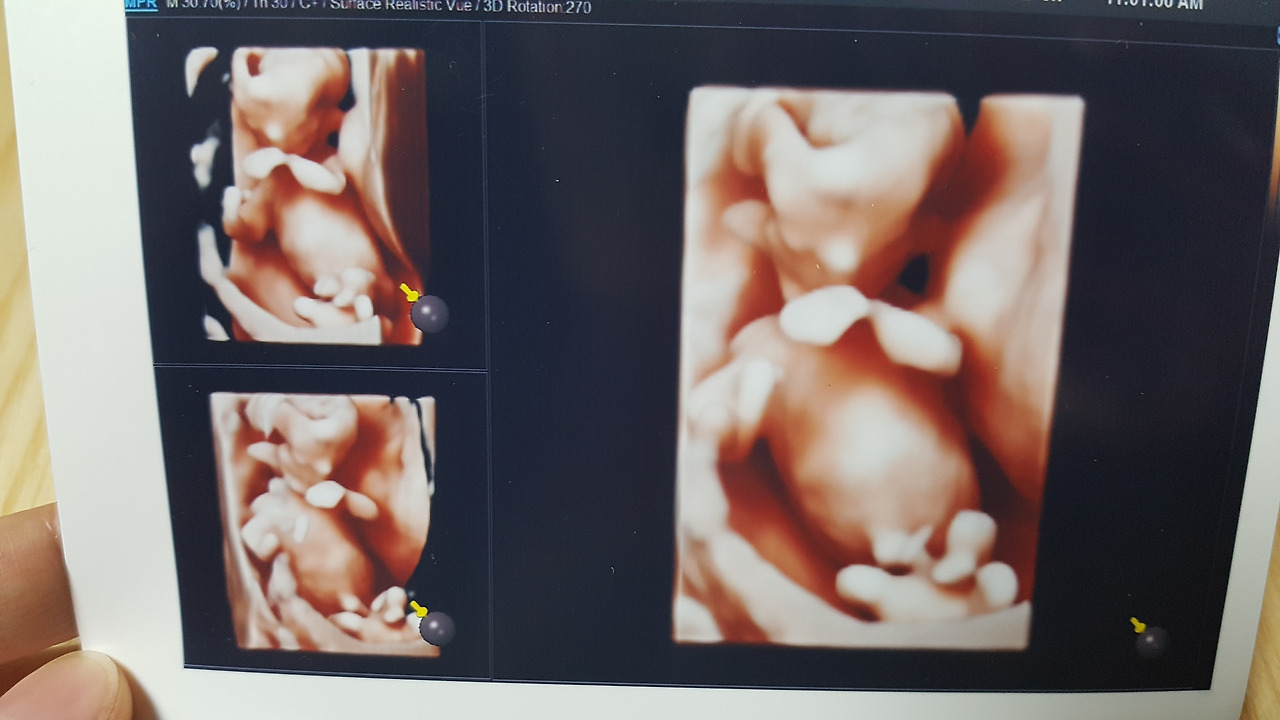

12/26 둘찌야 안녕!

ⓒ Lyn, Home